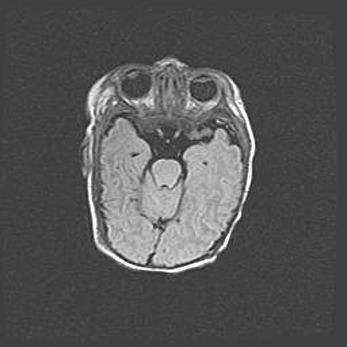

Множественные кисты обоих полушарий головного мозга, наибольшая из них в правой затылочной области. Ассиметричная атрофическая гидроцефалия.

Возраст: 7 месяцев

Вес: 5660 г

Пол: мужской

Окружность головы: 41,5 см

Срок гестации: 28-29 недель

Кисты головного мозга развиваются в результате многоочаговых некрозов вещества мозга и возникают вследствие перенесенной перинатальной инфекции, менингитов, энцефалитов, асфиксии, родовой травмы, расстройств мозгового кровообращения различного генеза. Образованию кист в веществе головного мозга плодов и новорожденных способствуют такие факторы, как высокое содержание в нем воды, недостаточная (или отсутствие) миелинизация и слабая астроглиальная реакция на повреждение.

Кисты могут сочетаться с гидроцефалией и другими поражениями головного мозга.